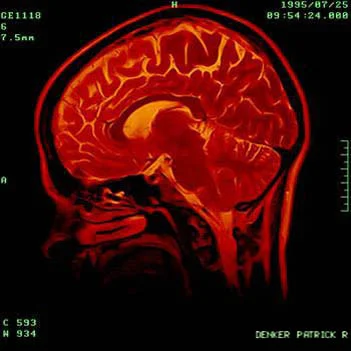

He believed this was because the High-resolution 7-Tesla fMRI scanner used to scan the brain is incredibly noisy, making it difficult for subjects to distinguish basic tones. This problem is made worse because electrical devices are banned inside the scanner, so the sound is effectively “piped” into special headphones. But when listening to music the subjects naturally "fill in" some of the missing parts.

The scanner works by registering the level of oxygen in the blood in certain areas of the brain divided into 3D units called voxels. By testing a number of subjects on different genres of music they were able to see a pattern build up. From this they created a model which they used to read brain scans and reproduce the sounds the subject thought about - a kind of reverse engineering.